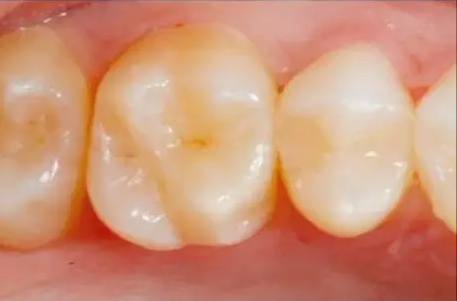

圖8顯示了去掉成形片之前牙釉質(zhì)層充填完成的修復(fù)體。

一旦完成拋光,最后一步就是涂上表面封閉劑(Seal and Shine,Pulp-dent),在微米水平封閉和保護(hù)修復(fù)體邊緣界面任何可能由于器械無(wú)法接觸到而存在的細(xì)微缺陷要記住,探針最多能夠“察覺(jué)”到30微米的邊緣縫隙。而細(xì)菌的直徑是1微米。封閉劑能夠封閉這些細(xì)小縫隙。圖12顯示了II類(lèi)洞復(fù)合樹(shù)脂修復(fù)體完成后的咬合面觀。